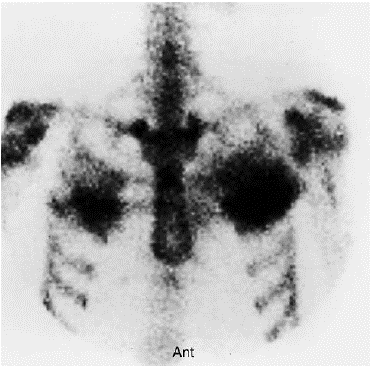

Homem de 25 anos, com história familiar de neoplasia de próstata, está sendo investigado por episódio de dor importante e persistente na região torácica anterior após ter realizado um treino de Crossfit. Baseado nos achados da cintilografia óssea abaixo, o diagnóstico mais provável é: